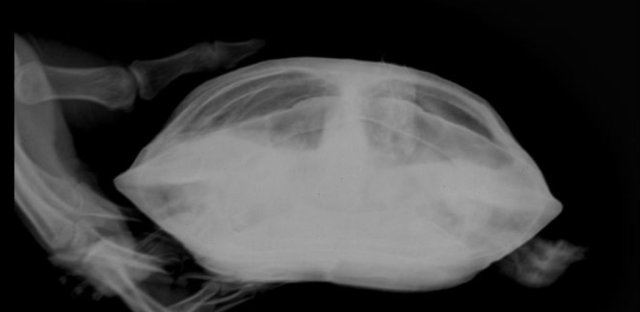

Елена_F Ваше имя: Цып Локация: Россия. г.Курск Опубликовано: 20 марта 2025 Автор Опубликовано: 20 марта 2025 @moth А по рентгену можно что- то сказать? Вроде газов меньше стало.

Консультанты moth Ваше имя: Мария Локация: Москва Опубликовано: 20 марта 2025 Консультанты Опубликовано: 20 марта 2025 @Елена_F врач расшифровку рентгена ещё не делала? по мне лучше стало, но надо чтобы врач смотрела и расшифровала, потому что здесь ошибка будет очень дорого стоить

Елена_F Ваше имя: Цып Локация: Россия. г.Курск Опубликовано: 20 марта 2025 Автор Опубликовано: 20 марта 2025 @moth Расшифровку она не делала, но для сравнения я ей показала старый снимок и она мне показала, что на новом снимке меньше затемнений, т.е. газы уходят. С сердцем тоже вроде всё нормально, осмотрела язык.